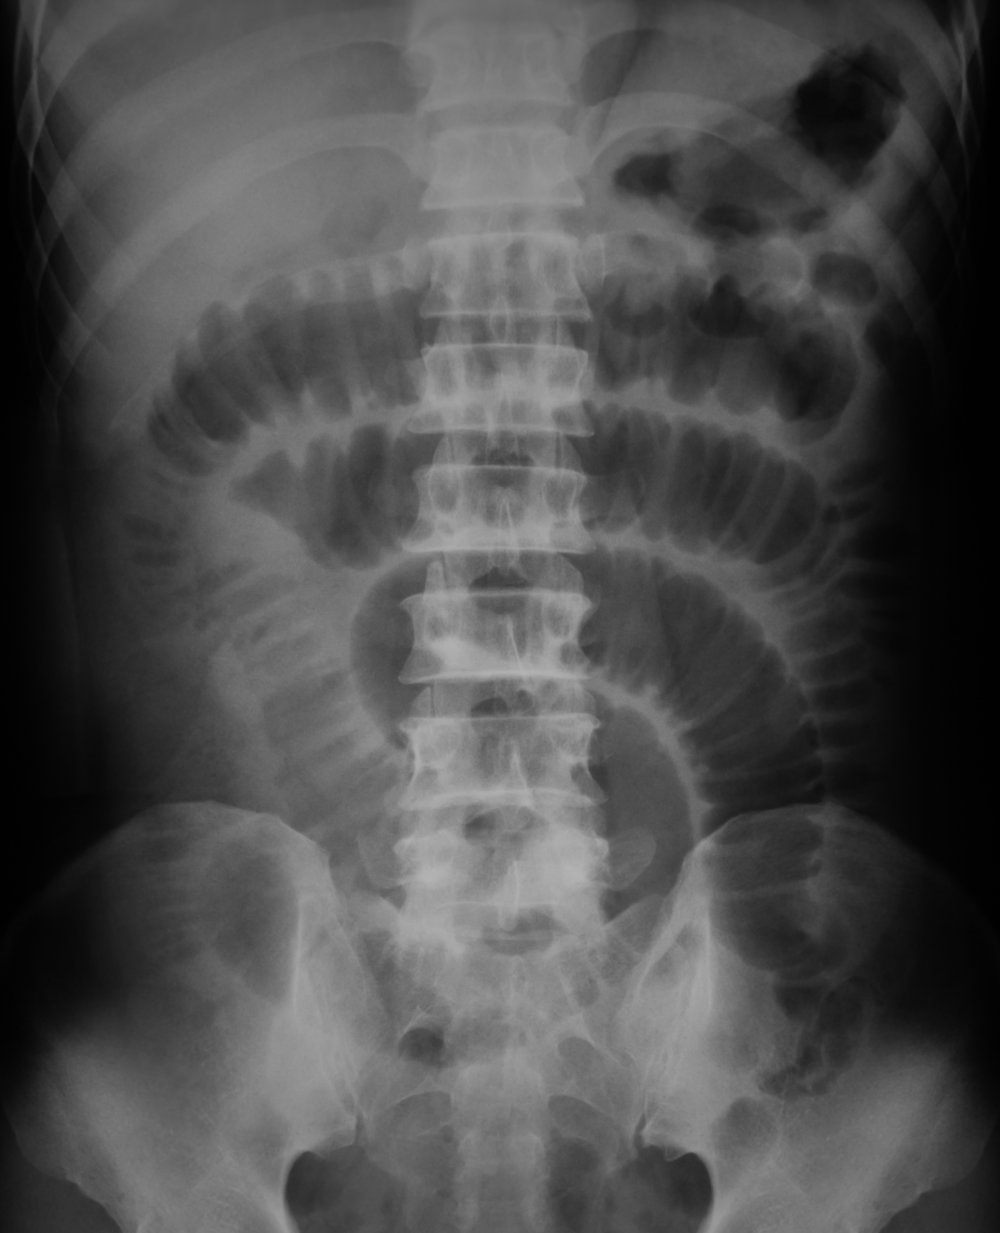

• El estudio radiológico de elección para confirmar el diagnóstico son radiografías simples en decúbito dorsal y de pie, la placa simple en decúbito dorsal muestra asas del intestino delgado dilatadas (más de 3 cm de diámetro), éstas pueden ser múltiples y en diferentes partes del abdomen, o sólo una o dos en un sitio específico.

• Niveles hidroaéreos: Signo de pila de monedas

• Asas dilatadas (asa proximal): Intestino Delgado > 3 cm e Intestino Grueso > 5 cm de diámetro. Asas colapsadas o de calibre normal asa distal.

• Cuando existe necrosis intestinal la radiografía evidencia asa intestinal inmóvil a los cambios de posición y su contenido lleno de gas (negro)

• Signo del grano de café: Cuando la causa es un vólvulo del sigmoides